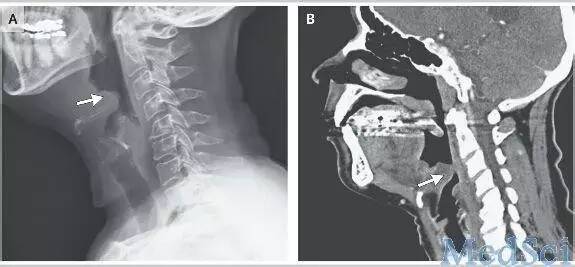

喉镜下,该病人会厌已肿胀如球,如水泡一样,紧贴咽后壁,喉入口已被遮挡。若不及时处理,很有可能一下子呼吸困难窒息而死。

口咽部检查多无明显改变,易被忽略,但是剧烈咽痛无法解释。只要采用间接喉镜检查,即可发现会厌明显充血、肿胀、严重时呈球形。如会厌脓肿形成,红肿黏膜表面可见黄白色脓点。由于肿胀会厌遮盖,声门是看不到的。